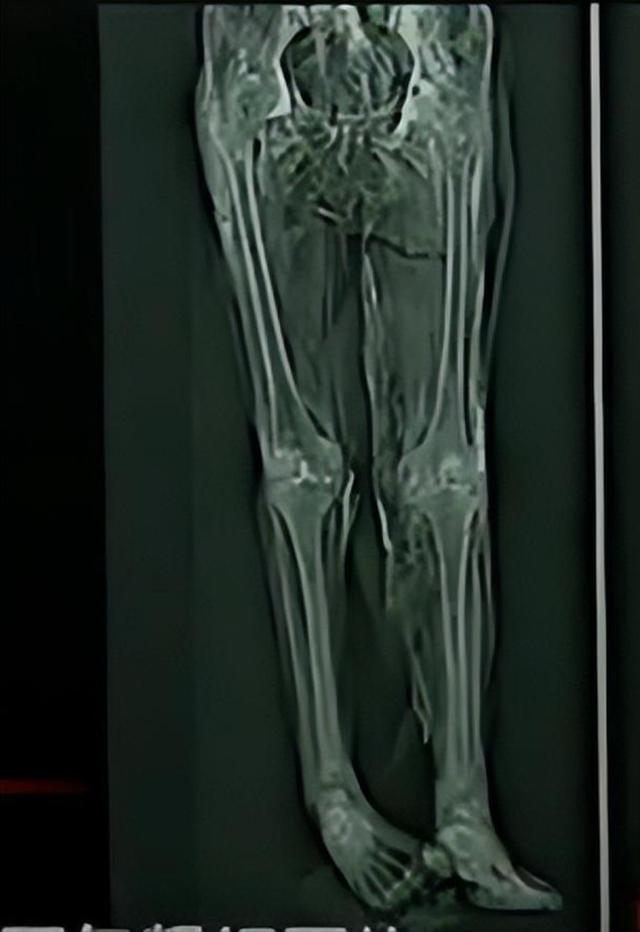

女尸的年龄应该有50多岁,身高大约在1.60米,全身的肌肤保存得十分完整,身体具有弹性,五脏六腑均未腐烂,甚至能够清晰地看到体内的血管。

凌惠平在下葬前有被反复捆绑过的痕迹,面部狰狞,舌头长长地伸在外面,很像传说中的吊死鬼,十分吓人,而且在其右腹部发现了一道长达五厘米的伤口,在其右脚处发现有受伤的痕迹。

首先,凌惠平腿部的伤口属于挫伤,应该是在生前有过长时间的病史,使得脚部骨骼已经出现了变形,但是这处伤口并不足以危害生命。

同时,根据对凌惠平脚底和膝盖磨损程度的观察,也证实了其生前的地位,走路的次数可以说是屈指可数。

其次,凌惠平身上的捆绑痕迹应该是在其死后下葬之前才有的,因为除了部分肌肉在长时间的捆绑下已经发生变形,其肩部骨骼也出现了凹陷,可是在其身体上并没有发现曾剧烈挣扎的迹象。

最后,凌惠平右腹部的伤口成为了大家关注的焦点,按照伤口的长度以及方向来看,很有可能是由利器所致,足以致命!

工作人员再次对凌惠平的内脏进行了检查,可结果与第一次一样,内脏保存良好,没有发现撕裂或破损,也没有找到恶性疾病的迹象,因此,可以基本排除凌惠平死于谋杀的假设。